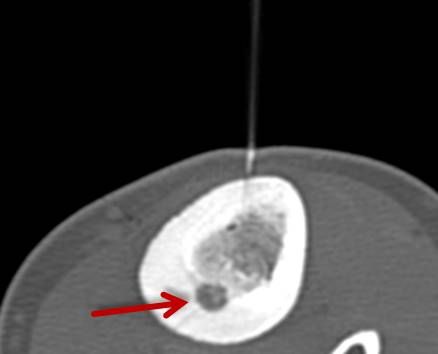

Abbildung: Bei der perkutanen Thermoablation von Lungentumoren werden spezielle Applikatoren unter CT-Bildgebung in den Zieltumor eingebracht. Durch Hitze wird der Tumor dann zerstört.

Die minimalinvasive Thermoablation ist auch eine Therapieoption für Lungentumore. Damit ein Lungentumor mit diesem Verfahren effektiv und sicher behandelt werden kann, sollten bestimmte Bedingungen (wie Größe, Anzahl und Lage) erfüllt sein. Ob diese Voraussetzungen gegeben sind, wird das Vorgehen vor der Therapie mit Kollegen aller für diese Fragestellung relevanten Fachdisziplinen besprochen.